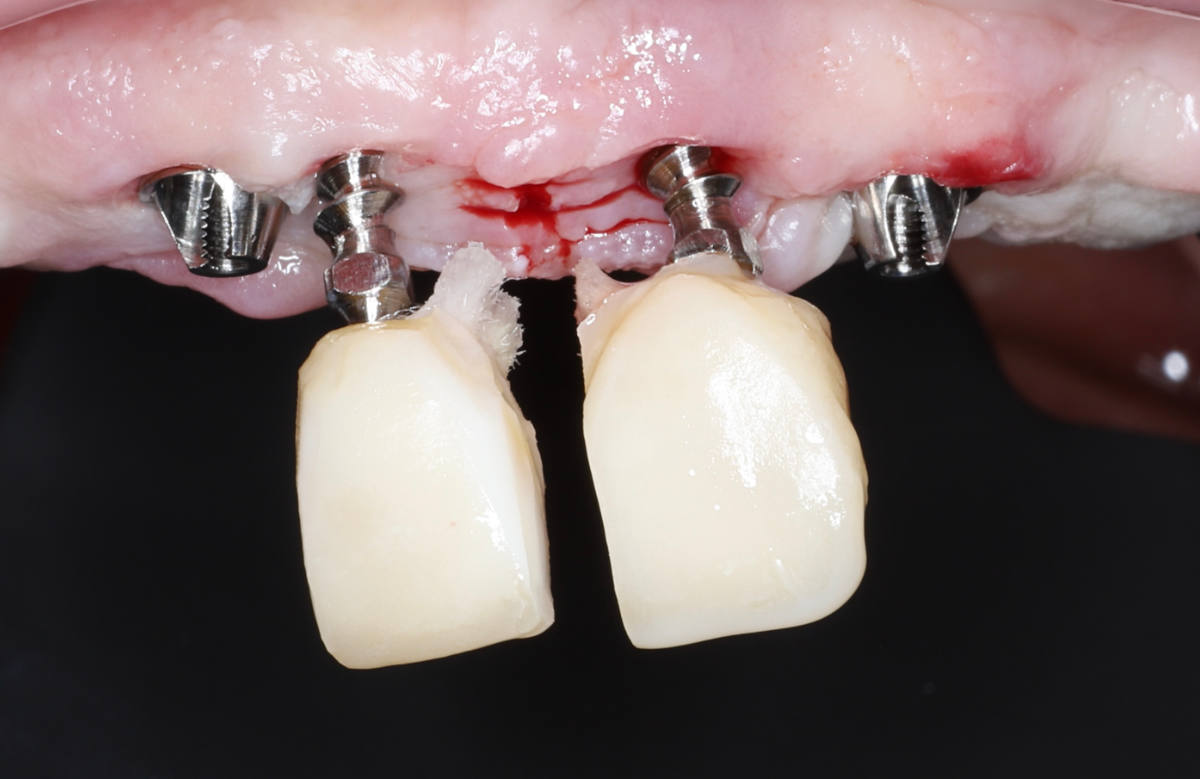

Navigovaná chirurgia, 5 implantátov

Autor práce Dr. Michal Repaši

Zubný technik Vasil Csopej